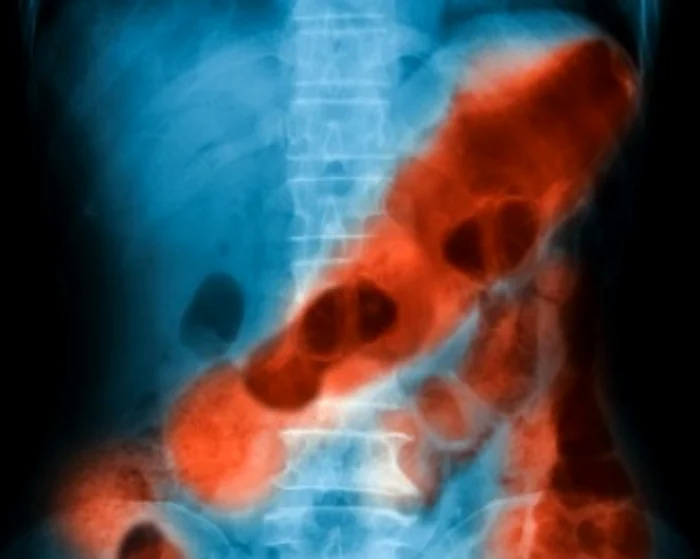

Hemoragia, care înseamnă pierdere de sânge, poate fi externă şi vizibilă sau internă, adică sângerarea se produce în interiorul unui organ, a unui muşchi sau a unei cavităţi a corpului. În cadrul hemoragiei digestive, sângerarea poate să apară în orice segment al tubului digestiv - esofag, stomac, duoden, intestin subţire sau colon. În acest caz, eliminarea sângelui se face fie pe gură, prin vomă, fie prin scaun.

În funcţie de locul unde se produce sângerarea, hemoragiile digestive pot fi: superioare (sângerare la nivelul esofagului, stomacului sau a unei părţi din duoden) sau inferioare (la nivelul intestinului subţire sau a colonului. Sunt mai rare decât cele superioare şi, de obicei, mai puţin grave.

În funcţie de severitatea sângerării, deosebim: hemoragia digestivă acută (prin care se pierde o cantitate mare de sânge într-un timp scurt) sau cronică (se pierd cantităţi mici de sânge, în mod repetat, într-o perioadă îndelungată). Aceasta este frecvent întâlnită, dar, fiind o sângerare redusă cantitativ, poate să treacă neobservată. Pot fi cauzate de ulcer sau varice Cele mai frecvente cauze ale sângerării gastrointestinale superioare sunt ulcerul peptic, varicele esofagiene şi eroziunea gastrică acută, provocată de obicei de excesul de medicamente. În unele cazuri, ea poate indica însă şi prezenţa unui cancer. Cele mai frecvente cauze ale sângerării gastrointestinale inferioare sunt hemoroizii şi fisura anală, dar şi cancerul rectal. Cum se manifestă Fiecare tip de hemoragie digestivă prezintă simptome specifice. Astfel, hemoragia digestivă superioară se manifestă prin: